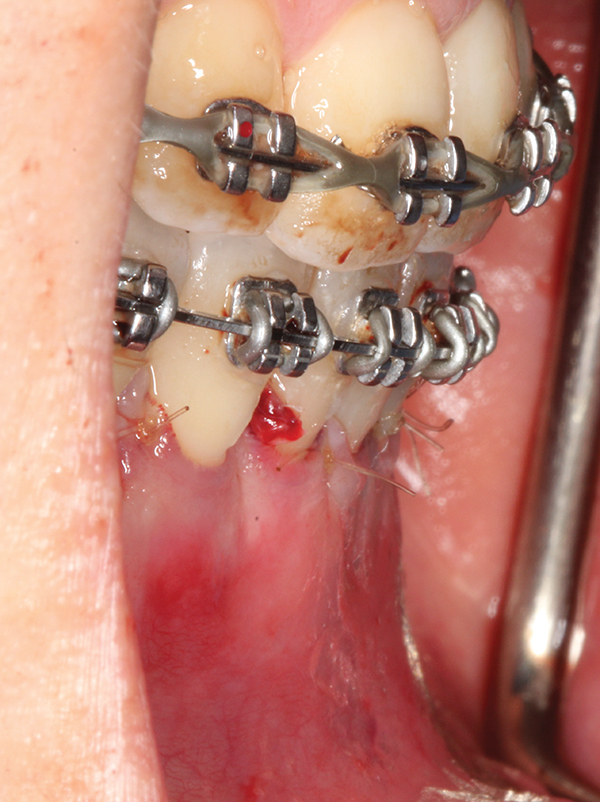

Fig 2. Full-thickness flap reflection. Note

dehiscence and fenestrations throughout. Orthodontic walls are limited to nonexistent.

Figure 2

Fig 3. Corticotomy cuts performed.

Figure 3